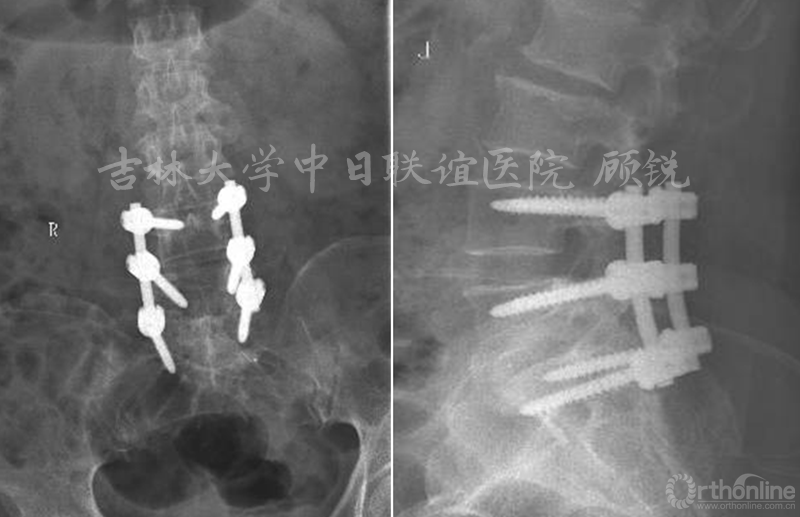

患者术后腰部疼痛及左下肢放射痛消失;每日2g头孢曲松钠静脉滴注3天;补液预防低颅压;第一日引流量300ml暗红色血性液体,第二日100ml淡红色血性液体,第三日40ml淡红色血性液体,拔除引流管;术后第6天,患者行腰部支具保护下地。

术后X线: